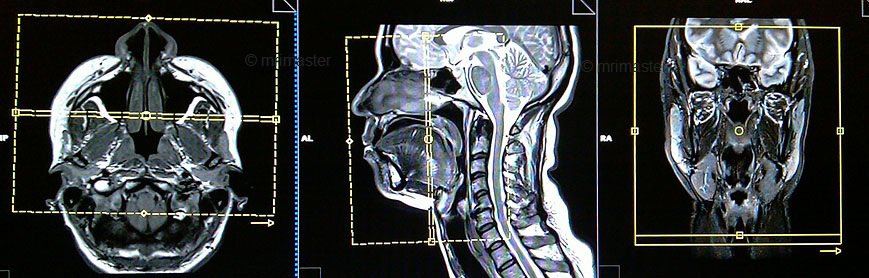

Chụp cộng hưởng (MRI) từ vùng đầu – mặt cổ là phương pháp có giá trị cao trong khảo sát xương, phần mềm vùng đầu- mặt- cổ.

Hình ảnh có được sau chụp MRI có độ sắc nét và tương phản rõ ràng đặc biệt trong các chỉ định khảo sát mô mềm. Thông qua các thuật toán dựng hình, MRI có khả năng tái tạo hình ảnh 3D để giúp bác sĩ quan sát cơ quan khảo sát thực tế và rõ ràng hơn.

- Phim chụp phải đạt được những yêu cầu hiện hình rõ các cấu trúc giải phẫu vùng mặt – vùng cổ trên các chuỗi xung được lựa chọn;

- Phát hiện vị trí, kích thước, mật độ của tổn thương;